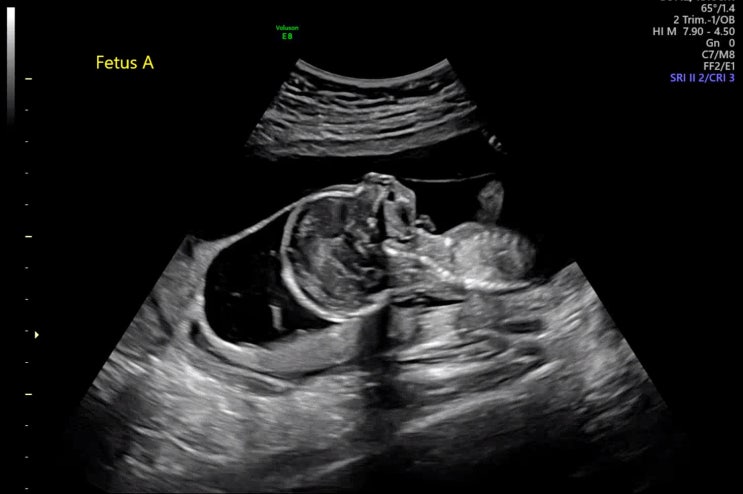

#11 [임신15주차] 쌍둥이임신 / 성별확인 / 아들둥이 / 사이판여행 / 토퍼제작 / 가랜드 제작 / 사이판켄싱턴호텔

7/8 오랫만에 남편이랑 같이 산부인과에 다녀왔다. 7/17에 강남차병원 예약이 있긴 했지만 사이판에 가기전...